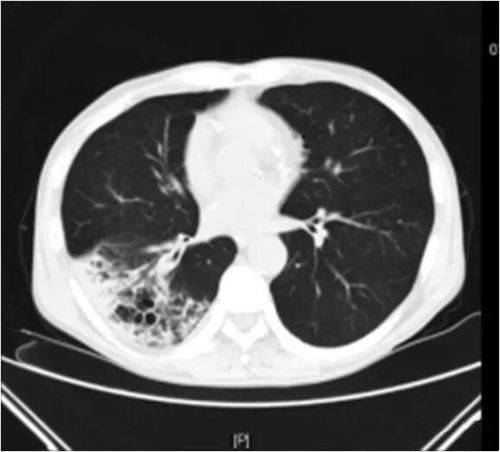

大叶性肺炎ct报告,大叶性肺炎ct

大叶性肺炎并左肺上叶肺不张,请看胸部ct结果所示

「典型」肺炎链球菌大叶性肺炎不典型

大叶性肺炎ct图片

大叶性肺炎的ct图像

大叶性肺炎ct影像图

大叶性肺炎ct影像表现

大叶性肺炎

大叶性肺炎ct典型图片

大叶性肺炎影像

大叶性肺炎图片